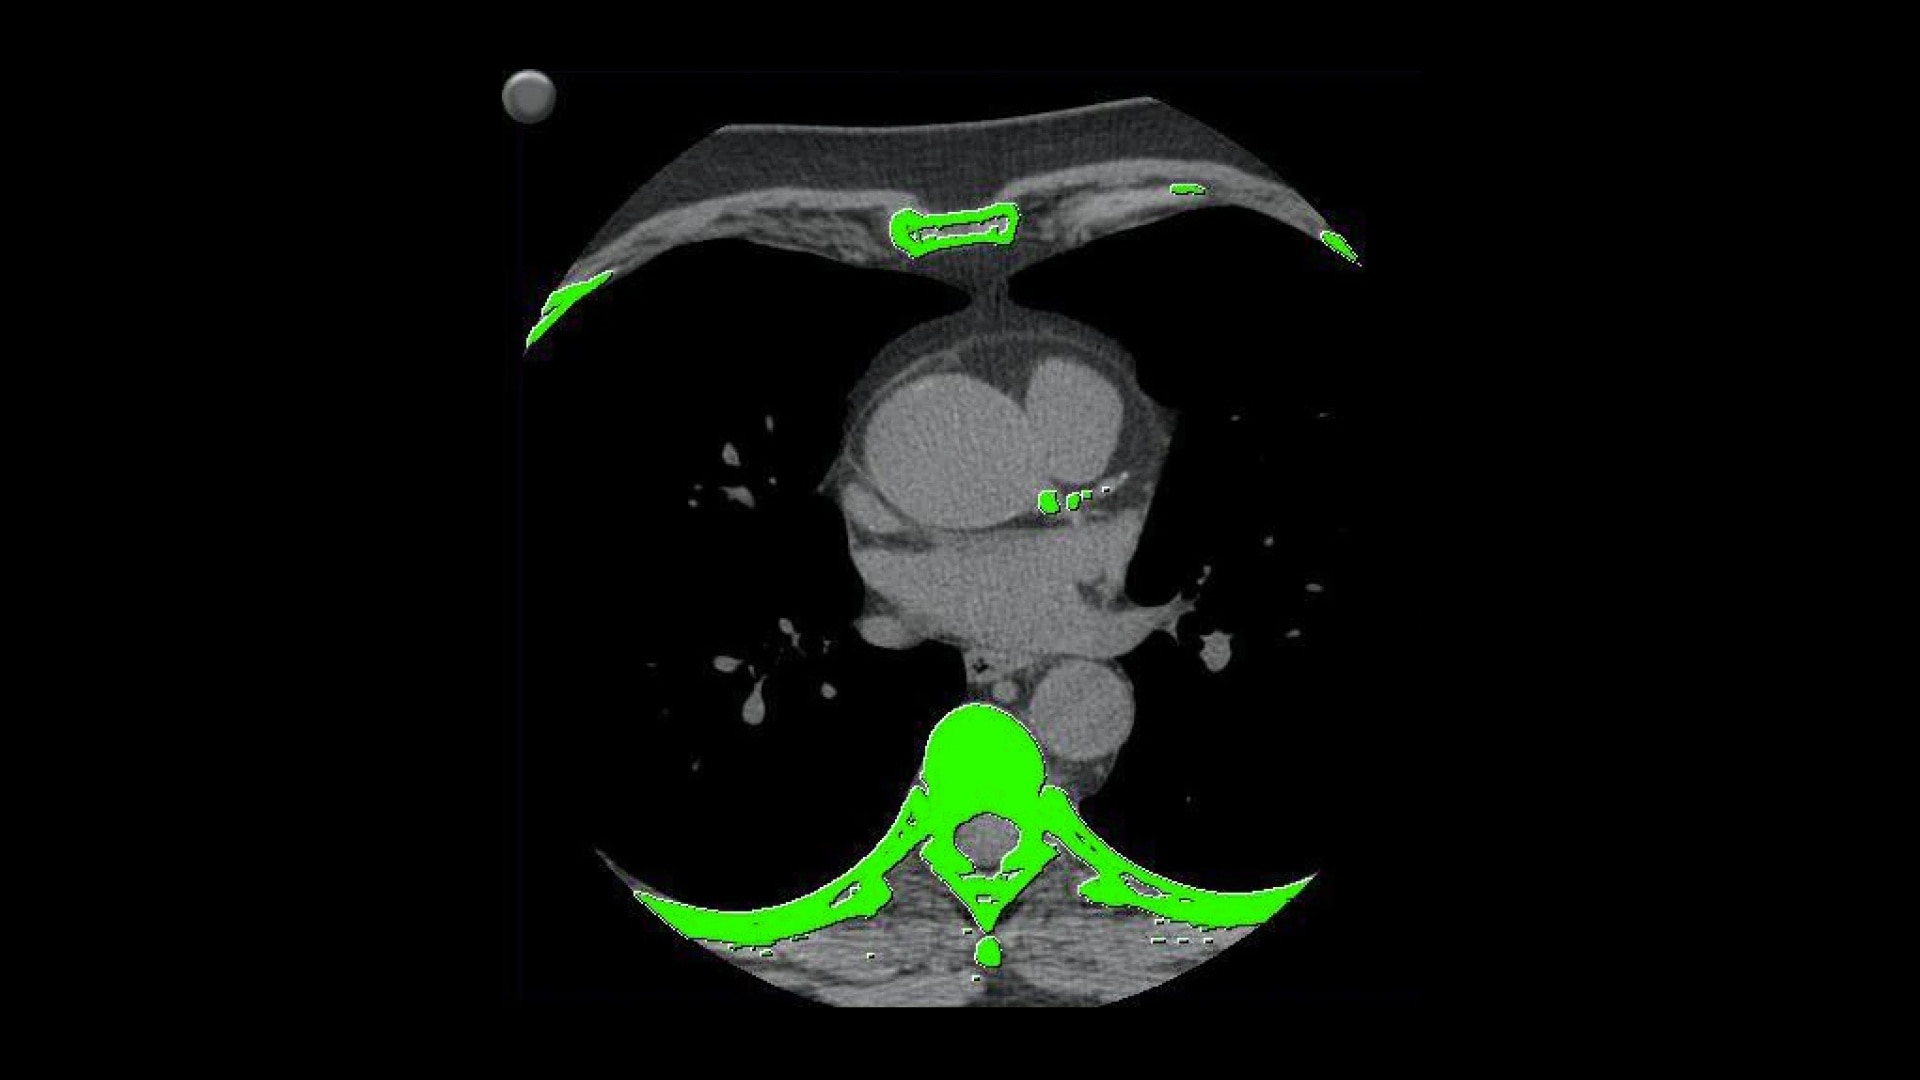

• Automatically detects calcium and highlights it in green

• Volume scoring calculates volumes (mm3) of calcified plaque above the 130 HU threshold

• Mass scoring calculates mass (mg) of calcified plaque above the 130 HU threshold